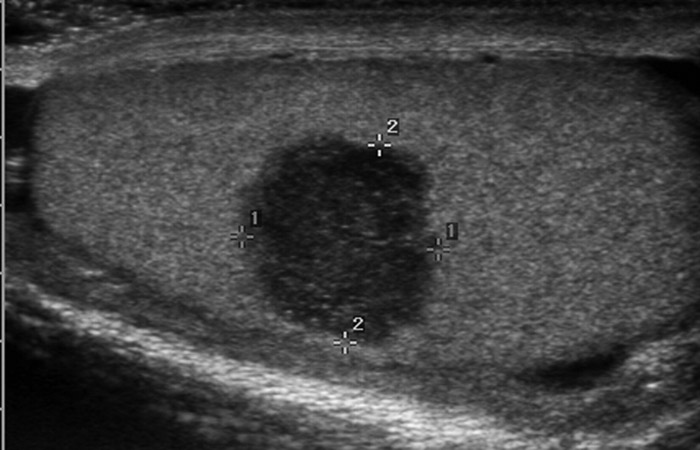

Με το υπερηχογράφημα του οσχέου ελέγχονται οι όρχεις και οι επιδιδυμίδες για την ανάδειξη τυχόν φλεγμονώδους διεργασίας (ορχίτιδα- επιδιδυμίτιδα), εστιακής βλάβης (π.χ. νεοπλασία), μετατραυματικών αλλοιώσεων, καθώς και για διαταραχές της αιμάτωσης (π.χ συστροφή όρχεως)